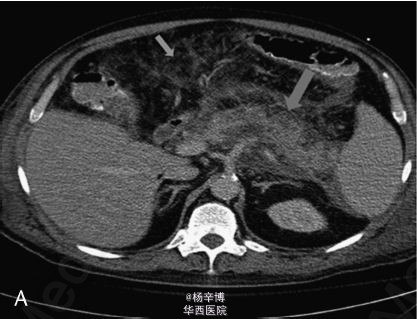

一59岁男性患者以严重腹痛、呕吐急性起病入急诊科,病史提示胆源性胰腺炎。体格检查:T 37.9℃,心率135次/分,呼吸32次/分,血压130/70mmHg,腹部肌紧张,广泛压痛及反跳痛。辅助检查:白细胞计数 24*10^9/L,血清淀粉酶 982IU/L,脂肪酶396IU/L,乳酸 2.2mmol/L,大便隐血阳性。遂诊断急性胰腺炎收入ICU。腹部CT示急性胰腺炎胰周广泛炎症,结肠旁沟游离积液,一钙化胆囊结石,未见胆管扩张或游离气体(图A)。患者症状逐渐加重,后行气管插管。即使给予了广谱抗生素,患者仍持续高热,在住院第11天复查CT示坏死性胰腺炎伴腹膜后近端结肠穿孔,可见肾旁前间隙渗出物及游离气体(图B)。讨论后行开腹探查术。术中见小肠和大网膜广泛粘连包裹降结肠左外侧壁。结肠穿孔位于结肠脾曲及近端降结肠。行粘连松解术及穿孔修补术后,予安置引流管及空肠造瘘,术后患者转入SICU。患者恢复较慢,手术2月后病情缓解出院随访。